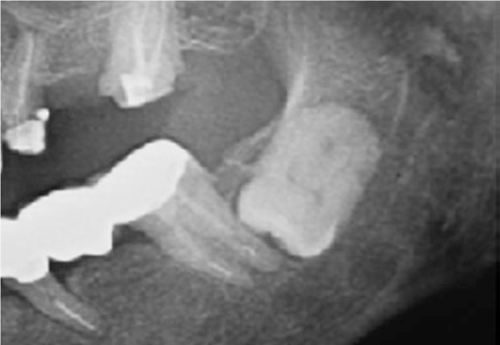

Jei protiniams dantims nėra galimybės tinkamai išdygti, nustatomas dantų susigrūdimas – tokia situacija yra ganėtinai pavojinga, nes susigrūdę dantys gali sukelti infekciją, lemti gretutinių dantų gedimą, dantenų ligas ar cistų formavimąsi. Kai siekiama išvengti šių problemų, odontologai rekomenduoja protinius dantis pašalinti. Prieš tai yra atliekama rentgeno nuotrauka, kuri padeda nustatyti dantų rovimo būtinybę.